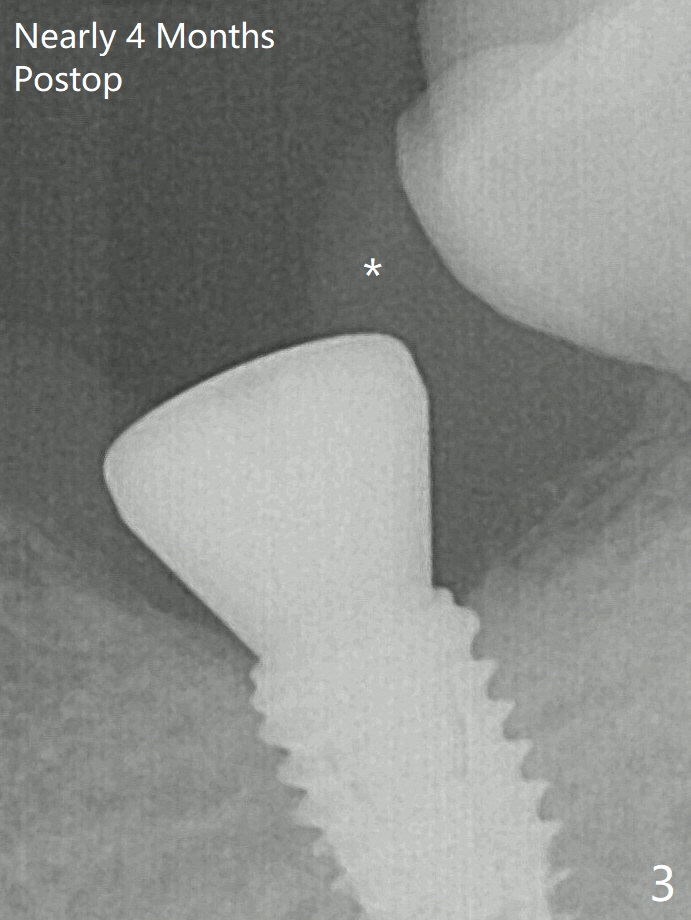

With 34 mg of Lidocaine and 17 mcg of Epinephrine (local infiltration), a 4.5x8.5 mm implant is placed with guide. The insertion torque is ~50 Ncm.  It is placed in precise depth and in a short period of time (tolerable to the operators and patient, easier than mini-implant placement, Fig.1).  Minimal bone resorption at the crest is noted nearly 4 months postop (Fig.3).  *: gingiva.